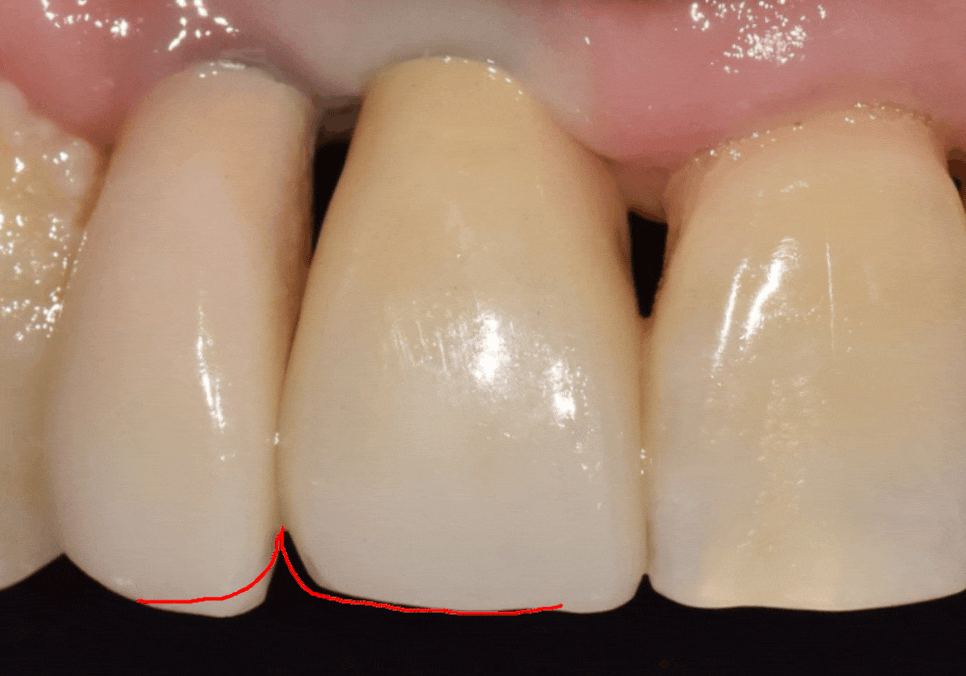

막상 보철물을 끼워보니 환자분께서

치아 길이가 약간 짧아 보이는 것 같다고

말씀하셨어요.

사실 치아 길이는 0.5mm만 차이가 나도

사람의 인상을 좌우할 만큼 예민한 부분인 만큼,

치아의 모양이나 길이는

옆 치아의 영향을 많이 받는 상대적인 영역이에요.

이전에 임플란트를 했던

오른쪽 앞니가 살짝 길다 보니,

중앙 앞니가 상대적으로 짧아 보였던 것이죠.

그래서 저희는 중앙 앞니

끝부분의 길이를 미세하게 늘려보기로 했어요.

1mm 정도의 아주 작은 변화였지만,